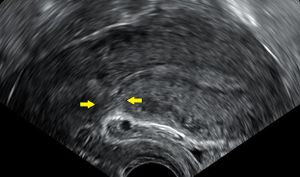

الولادة القيصرية (إنگليزية: Caesarean section)، هي عملية جراحية يتم فيها شق بطن الأم لولادة طفل أو أكثر، وغالباً ما تُجرى لأن الولادة المهبلية قد تعرض الطفل أو الأم للخطر.[2] تشمل أسباب اللجوء للولادة القيصرية الولادة المتعسرة، الحمل بتوأم، ارتفاع ضغط الدم عند الأم، الولادة المقعدية، ومشاكل في المشيمة أو الحبل السري.[2][3] تُجرى الولادة القيصرية بناءً على شكل حوض الأم أو تاريخ الولادة القيصرية السابقة.[2][3] من الممكن أن تلد الأم ولادة مهبلية بعد الولادة القيصرية.[2] توصي منظمة الصحة العالمية بإجراء العملية القيصرية فقط عند الضرورة الطبية.[3][4] تُجرى بعض الولادات القيصرية بدون سبب طبي، عند الطلب من قبل شخص ما، عادة الأم.[2]

تستغرق الولادة القيصرية من 45 دقيقة إلى ساعة.[2] يمكن إجراؤها باستخدام التخدير النخاعي، حيث تكون المرأة مستيقظة، أو تحت التخدير العام.[2] تستخدم القسطرة البولية لتصريف المثانة، ثم يُنظف جلد البطن باستخدام مطهر.[2] عادة ما يُجرى شق بطول 15 سم تقريباً أسفل بطن الأم. [2] ثم يُفتح الرحم بشق ثانٍ ثم يُولد الطفل.[2] ثم تُغلق الشقوق بالمخيط.[2] عادة يمكن للمرأة البدء في إرضاع وليدها بمجرد خروجها من غرفة العمليات والإفاقة.[5] في كثير من الأحيان، يلزم قضاء عدة أيام في المستشفى للتعافي بشكل كافٍ قبل العودة إلى المنزل.[2]